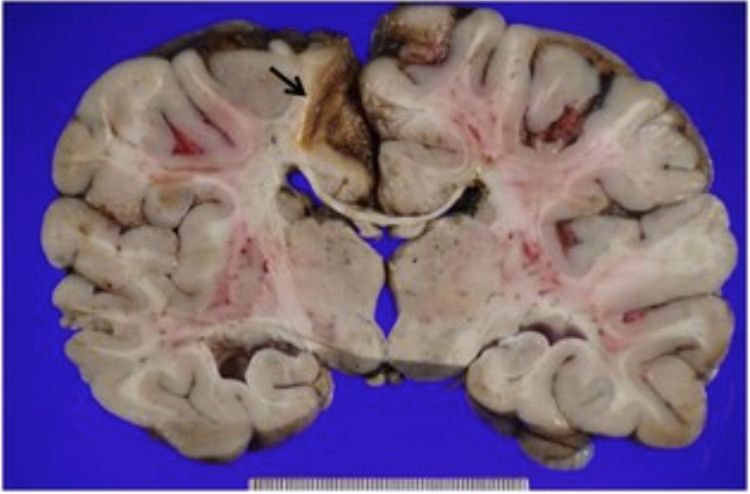

What artery is responsible for this infarct?

Anterior cerebral